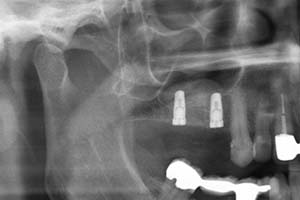

Ein weiterer oralchirurgischer Eingriff ist der sogenannte Knochenaufbau. Es bestehen viele Gründe wodurch ein Knochenaufbau, die sogenannte Knochenaugmentation, erforderlich werden kann. Eine fortgeschrittene Parodontitis kann zu Knochenrückgang in verschiedensten Bereichen des Kiefers führen. Die Knochenathrophie kann zudem auch durch Zysten im Kieferbereich erfolgen. Fehlende Zähne, die nicht durch Implantate ersetzt wurden, führen meist dazu, dass sich auch hier der Kieferknochen zurückbildet. Wenn herausnehmbare Prothesen schlecht und wackelig sitzen, kann der Vorgang des Kieferknochenabbaus noch verstärkt werden.

Knochenaufbauten oder sogenannte Kieferaugmentationen werden heutzutage sehr häufig durchgeführt. Von einfachen Maßnahmen nach einer Zahnextraktion zur Volumenstabilisierung bis hin zu komplexen Transplantationen körpereigenen Knochens führen wir bei uns in der Zahnärztlichen Praxisgemeinschaft Kampnagel verschiedenste Augmentationstechniken zum Kieferaufbau durch.

Bei einigen oralchirurgischen Operationen ist es in Sonderfällen möglich, dass kein eigenes Knochenmaterial verwendet werden kann, z.B. bei Sinusliftoperationen (Verbreiterung des Oberkiefers im Bereich der Kieferhöhle) oder bei einer Kieferkammverbreiterung. Hier versuchen wir stets als Alternative künstliches Knochenersatzmaterial zu verwenden um Ihnen ein zweites Operationsgebiet zu ersparen. Unter Umständen werden Membranen zur Fixierung des Augmentats benötigt.